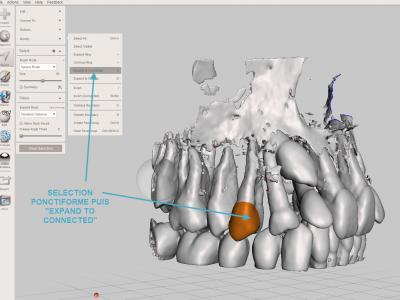

Pour éliminer les fragments non reliés : sélectionner une ou plusieurs petites zones à garder (dents par exemple) avec l'outil "Select" "Brush", puis opération "Expand to connected", puis inversion de la sélection avec la touche "I", puis les supprimer avec le raccourci clavier "X"